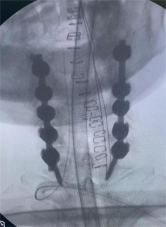

8. 机器人导航辅助下脊柱侧弯矫正技术

脊柱侧弯是一种复杂的脊柱三维畸形,其中以青少年特发性脊柱侧凸最常见。皇冠娱乐城

在浦口地区率先开展机器人导航辅助下脊柱侧弯矫正术,实现了脊柱侧弯手术准确、微创、智能化的突破,获得了良好的效果。还有老年人退变性侧弯,机器人亦可精准置入困难椎弓根螺钉,误差只有0.3mm。